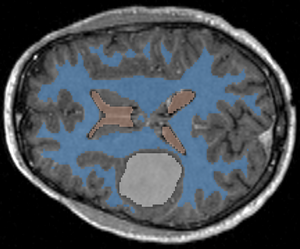

With Intensity Homogeneity set at 0.2, Smoothness at 0.05, and Number of Iterations at 1000, we get the following results:

Segmentation result, axial view

Segmentation result, sagittal view